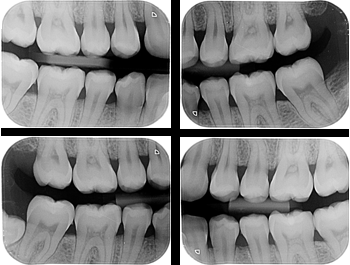

Ortho X - Radiografia Interproximais

É utilizada para pesquisa de cáries proximais e reincidentes, para relação cárie-câmara pulpar, adaptação de prótese, restabelecimento dos pontos de contato, estudo das cristas alveolares e verificação de nódulos pulpares.